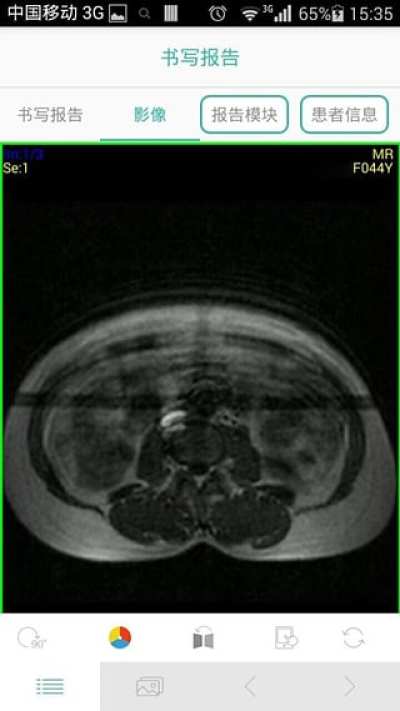

哒哒影像app是一款能够帮助医生们更加轻松的查看医学影像图片的免费手机软件。比如最为常见的X光片处理起来的工作量就很大,使用它的智能筛选就能够有效的减轻工作负担。

“哒哒影像”是由致力于改变影像科医生的工作现状,提升患者影像诊断体验,增强医疗机构的影像诊断水平的成都影达科技有限公司精心打造的一款适用于医学影像医生工作和学习的优质APP。

全像素高清显示;